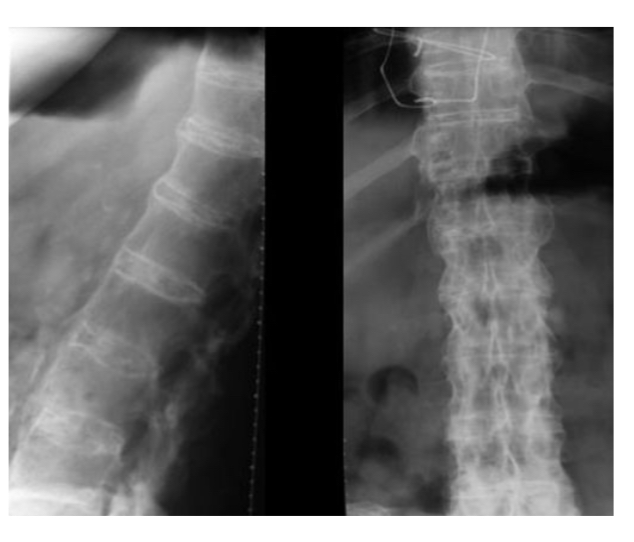

Maladie de Hodgkin

condensation diffuse d’un corps vertébral

Vertèbre « ivoire »